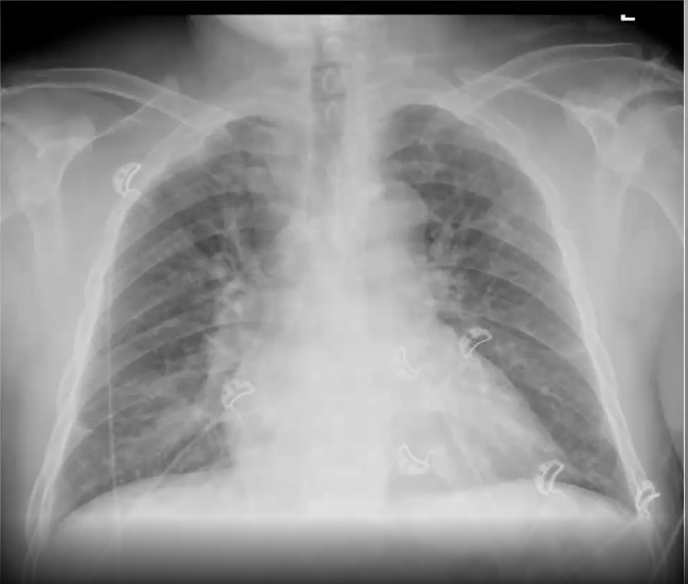

What’s your diagnosis?

Right lower lobe pneumonia because you have a right heart border (no silouhette sign) and a spine sign